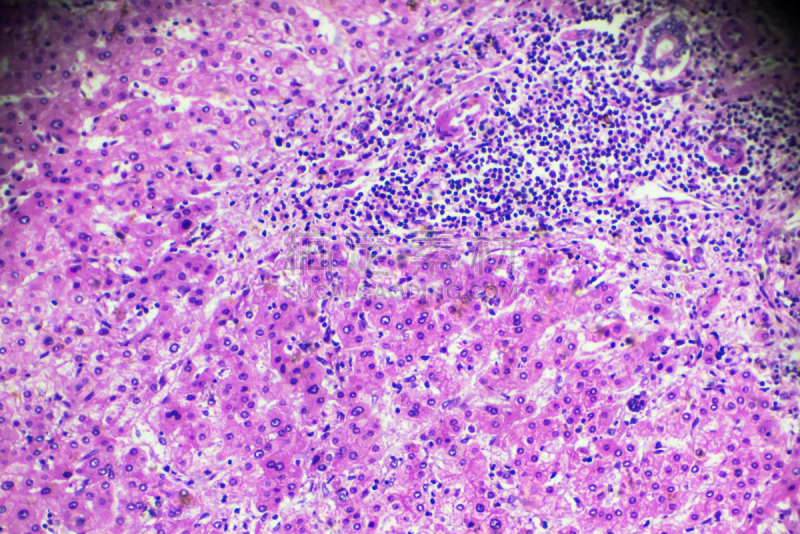

详情

JPG